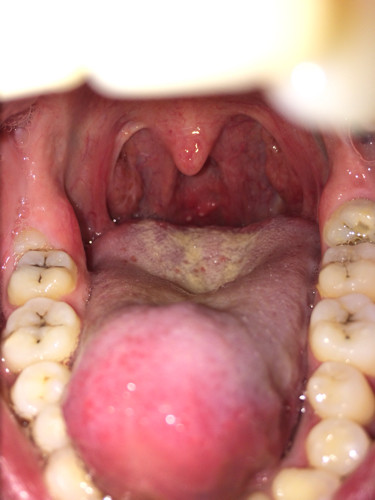

吐口水都痛,我现在状况是不是很严重啊. 有照片速度来看看

吃快卖榨菜肉丝,吃一半突然感觉口腔很痛,照片拍下来发现小舌头一边

小舌头长了两个红红的东西是怎么回事?

一直有异物感,看了下镜子吓到了,小舌头肿起来了,后面好像都发炎了,不

喝水,咽口水都疼是怎么回事,白色哪里像泡一样的是什么,小舌头周围

最近似乎感冒,咳嗽时后脑勺也会伴随着咳嗽痛,悬雍垂